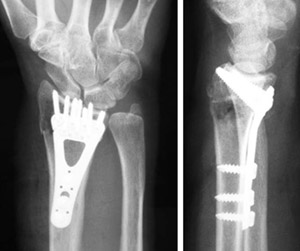

A plate and screws hold the broken fragments in position while they heal.

An external fixator.